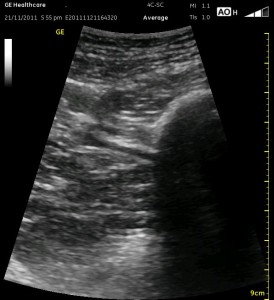

The following ultrasound image shows typical relationships of the sonoanatomy of the anterior sciatic nerve block. The femur is at 4cm on the right (lateral) of the image seen as a bright white horizontal line. Typically, there is a bone shadow below it, though there is some artifact below the femur here. The femoral vessels are seen between the 2cm and 3cm marks just to the right of center as a darkened area. They really can be determined by pausing for the appearance of arterial pulsation and venous compressibility. The adductors are seen to the left of the femur as a darkened area. Just deep to this between the 6cm and 7cm mark is a brightened rectangular shape, the sciatic nerve. The brightness fill fade with rocking of the probe over it. The nerve can be approached from the medial or lateral aspect of the probe, and moving the probe medially will sometimes allow for a better trajectory.

The image above is not an obvious one, and I did that on purpose. You have to get used to the idea that you will not always have a ‘super distinct’ image with this approach, and you will often need to use a number of additional clues to find your target and then to put local around it. I think the only way to really get a handle on being able to identify the basic elements is to look at several images over and over, so I have provided several below for you to use for practice. Note that the sciatic nerve will ‘poke out’ from behind the femur to different degrees depending on your orientation to the femur as well as to how far up or down the femur you go. It will be seen more if you are proximal. See how well you can identify the structures in the images below.